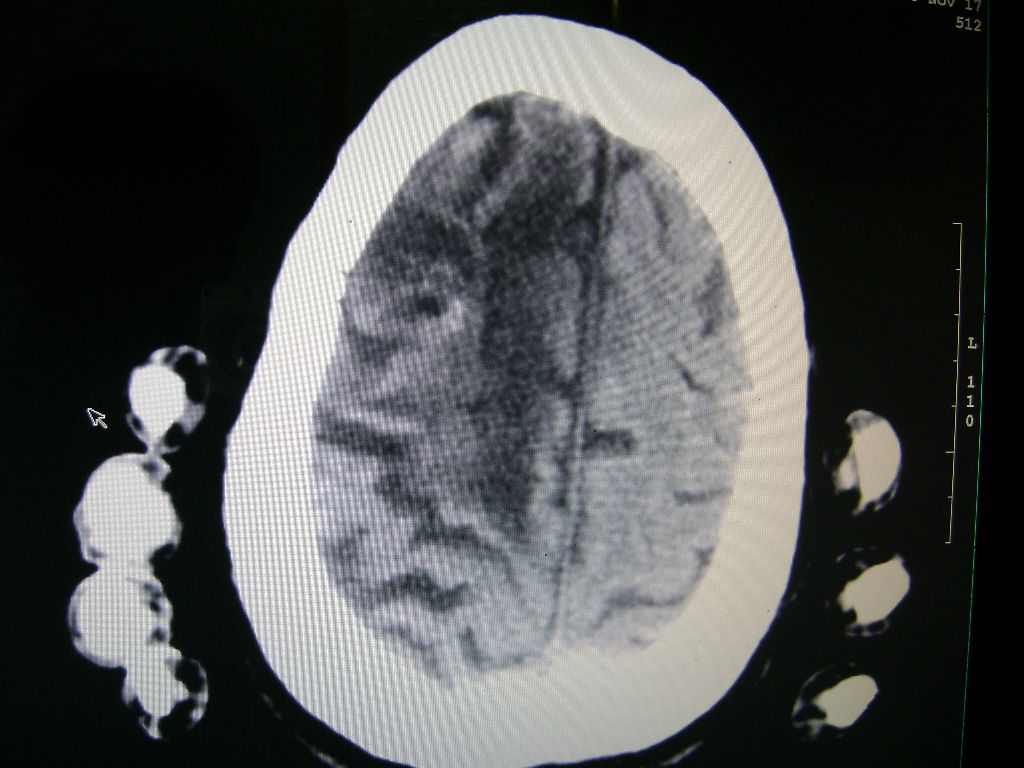

f 77 昏迷不醒

右侧额颞枕顶叶脑软化灶,脑萎缩,大脑中动脉壁钙化。

右脑软化灶,考虑再次梗塞,高密度灶出血?钙化?。。。量ct值,改窗宽,位

右脑软化灶,考虑再次梗塞,右顶叶高密度影不像是出血,密度很高,建议量ct值!

右侧半球陈旧性卒中,不除外伴有新病灶,左额叶梗塞,双侧大脑中动脉钙斑

右侧额颞枕顶叶脑软化灶,脑萎缩,大脑中动脉壁钙化。不支持出血(密度高,边界清且局限)顶枕区似有新发梗塞,建议核磁

1)右侧额颞枕顶叶脑软化灶;其内高密度影,多为钙化灶。2)脑萎缩。3)大脑中动脉钙化。

再次脑梗死,右侧额颞枕顶叶脑软化灶,高密度考虑钙化

右侧陈旧脑梗塞伴脑萎缩。脑内点状钙化。大脑中动脉壁钙化灶。无出血灶。

1)右侧额颞枕顶叶脑软化灶并钙化灶可能。2)脑萎缩。3)大脑中动脉钙化。 -